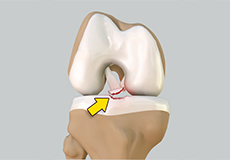

Patellar Instability

Any damage to the supporting ligaments may cause the patella to slip out of the groove either partially (subluxation) or completely (dislocation). This misalignment can damage the underlying soft structures such as muscles and ligaments that hold the kneecap in place. Once damaged, these soft structures are unable to keep the patella (kneecap) in position.

Patellofemoral Instability

Patellofemoral instability means that the patella (kneecap) moves out of its normal pattern of alignment. This malalignment can damage the underlying soft structures such as muscles and ligaments that hold the knee in place.

Patellar Dislocation/Patellofemoral Dislocation

Patellar dislocation occurs when the patella moves out of the patellofemoral groove, (trochlea) onto the bony head of the femur. If the kneecap partially comes out of the groove, it is called subluxation; if the kneecap completely comes out, it is called dislocation (luxation).

Recurrent Patella Dislocation

The patella (kneecap) is a small bone that shields your knee joint. It is present in front of your knee, on a groove called the trochlear groove that sits at the junction of the femur (thighbone) and tibia (shinbone). Articular cartilage presents below the patella and end of the femur cushion and helps the bones glide smoothly over each other when the legs move.